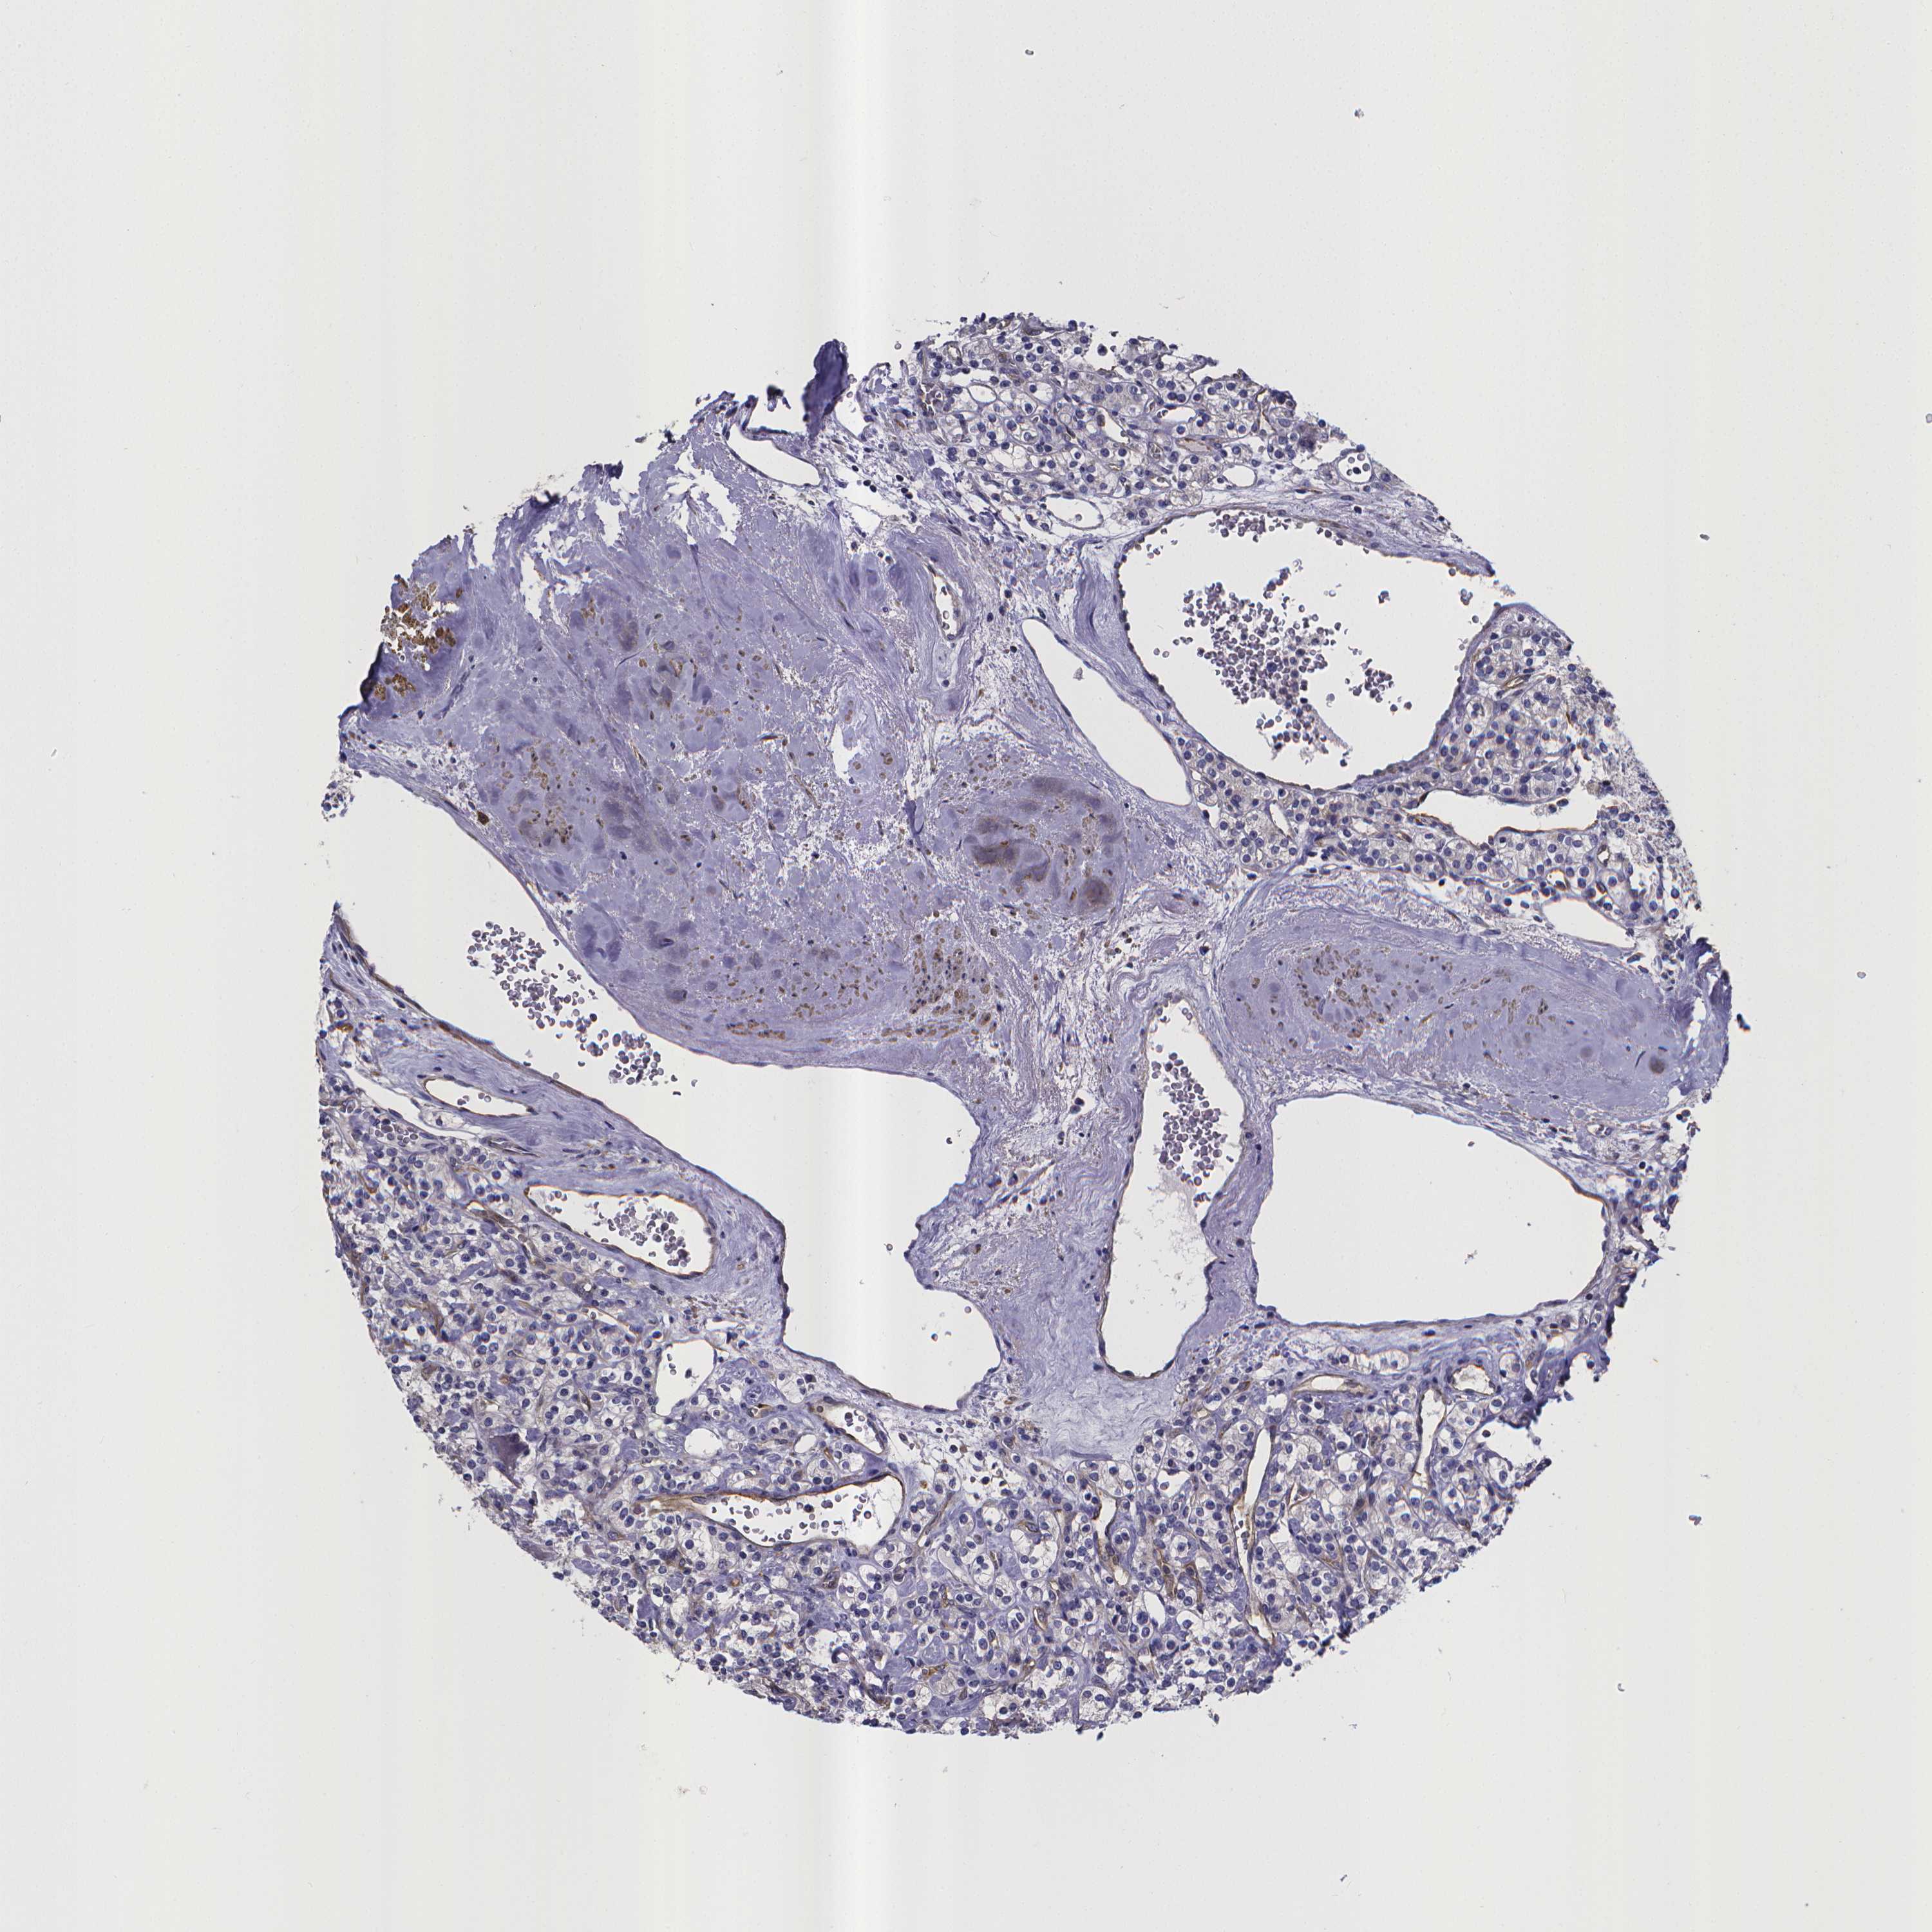

KIDNEY RENAL CLEAR CELL CARCINOMA (VALIDATION) - Interactive survival scatter ploti

RERG is not prognostic in Kidney Renal Clear Cell Carcinoma (validation)

: 17.98

Average pTPM 45.5

Number of samples 100